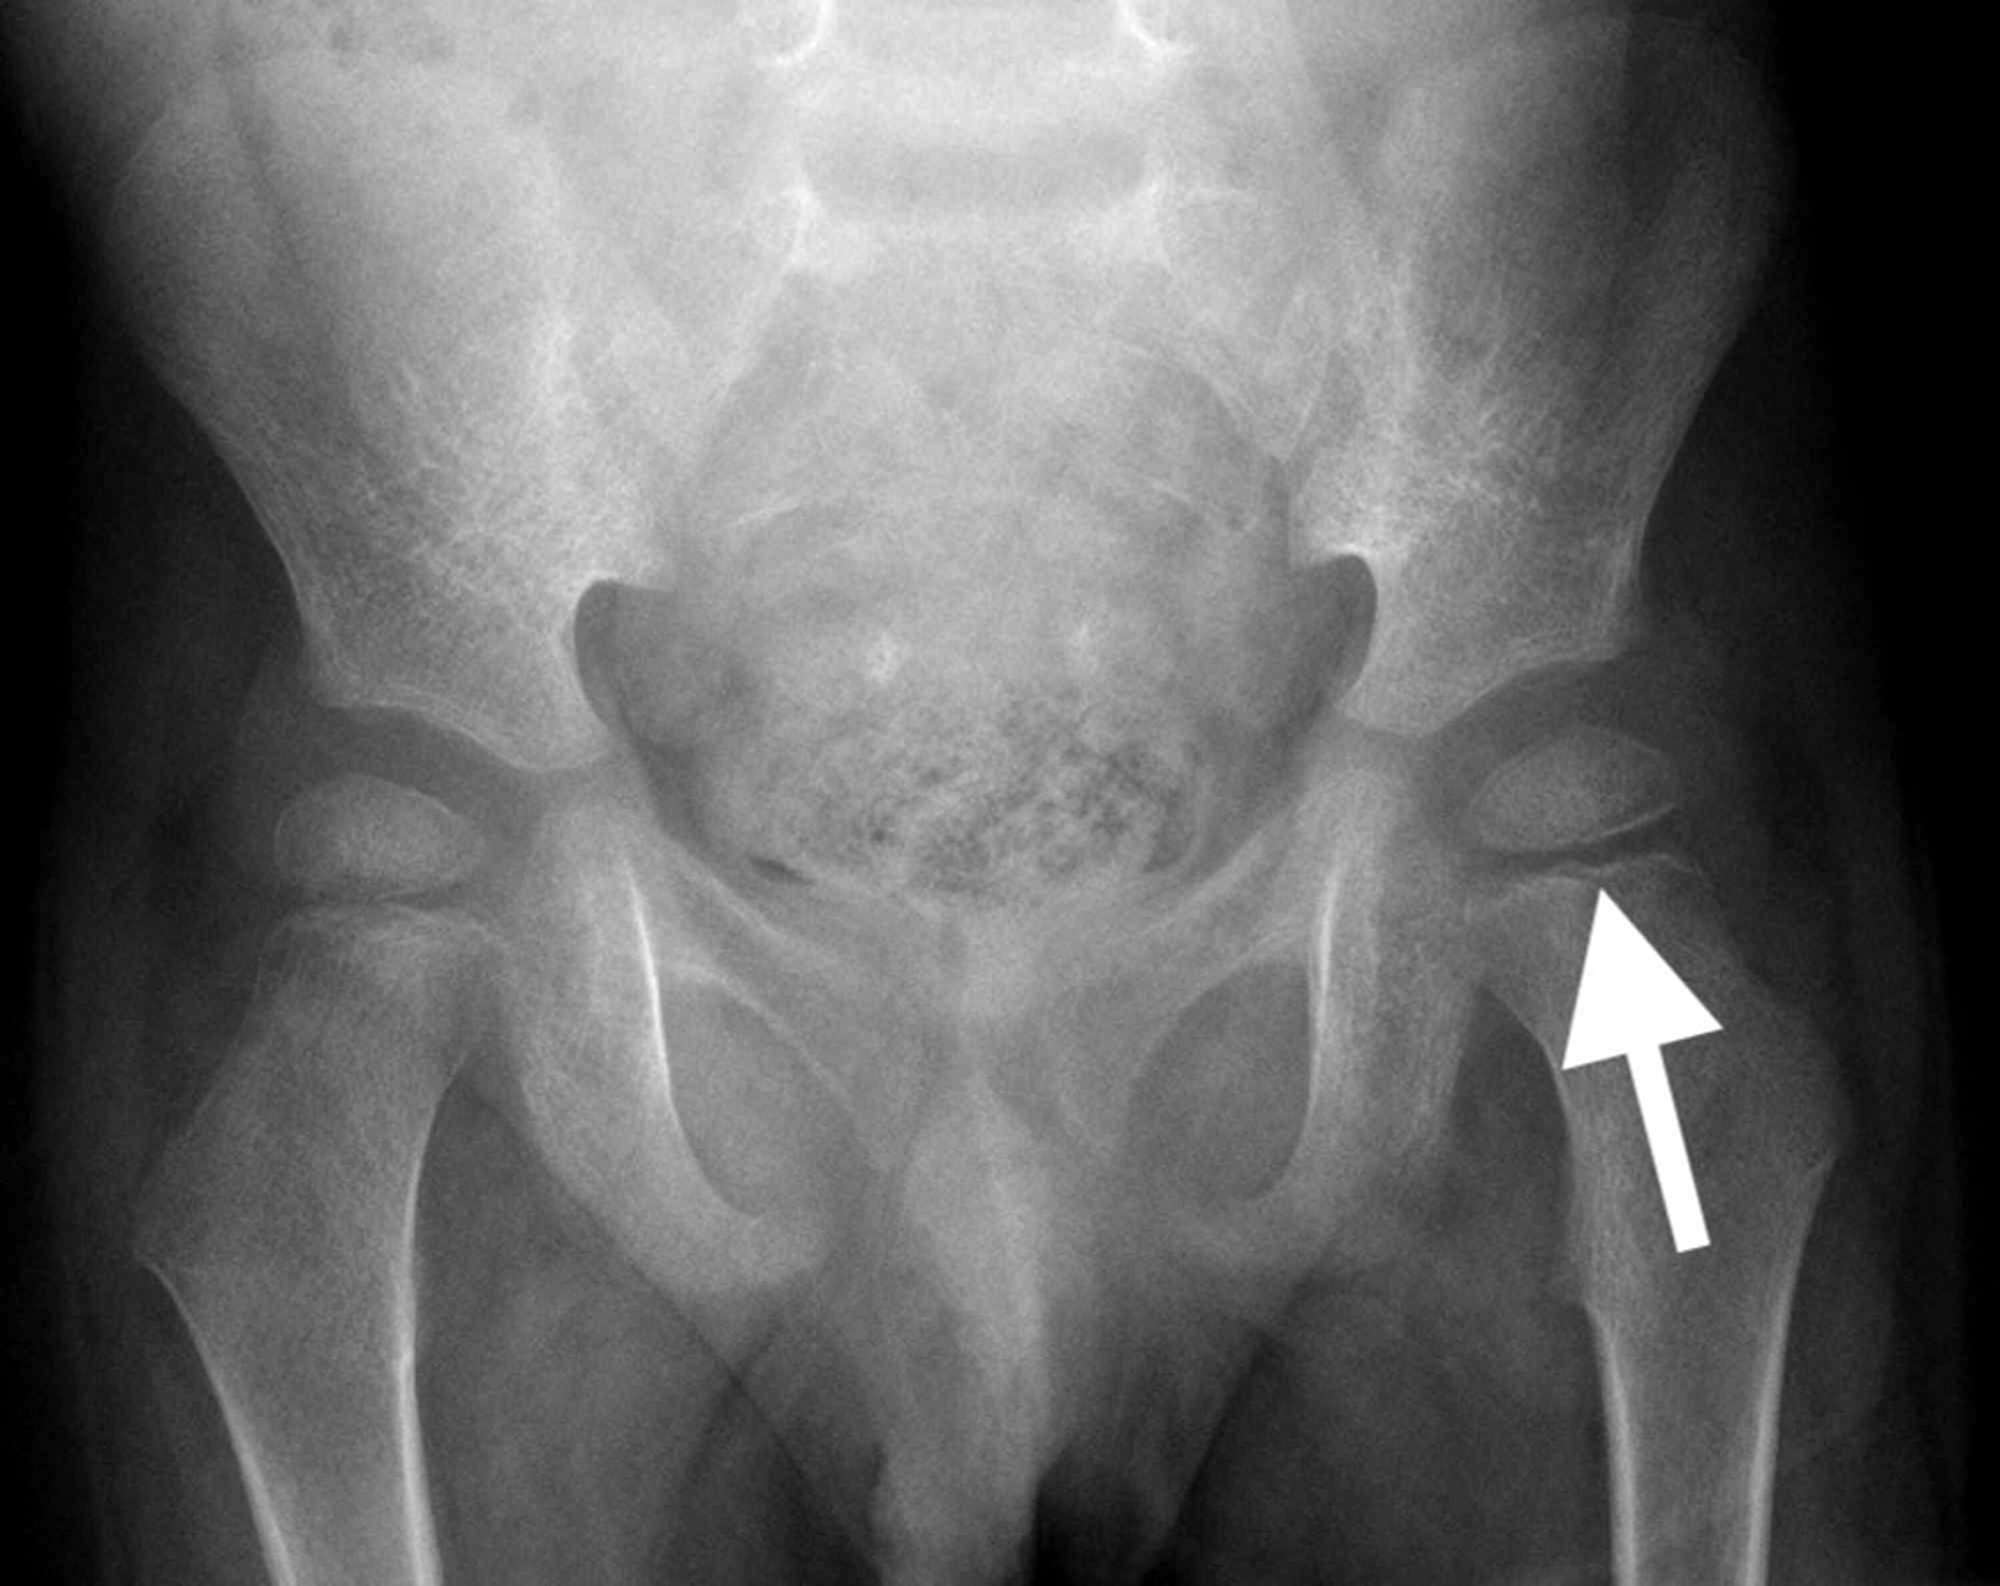

Cureus Vitamin C Deficiency Presenting as an Acute Limp in Childhood Vitamin C Deficiency Effect On Bones The bone resorptive effects of vitamin c deficiency result from both impaired osteoblast function and increased osteoclast. Reports of severe bone pain in maritime explorers suffering from scurvy during the 15 th century implied that vitamin c deficiency affects bone. On bone healing after tibial fracture (22,23,27), on. Vitamin c intake resulted in an increased expression of osteoblast differentiation genes. Vitamin C Deficiency Effect On Bones.